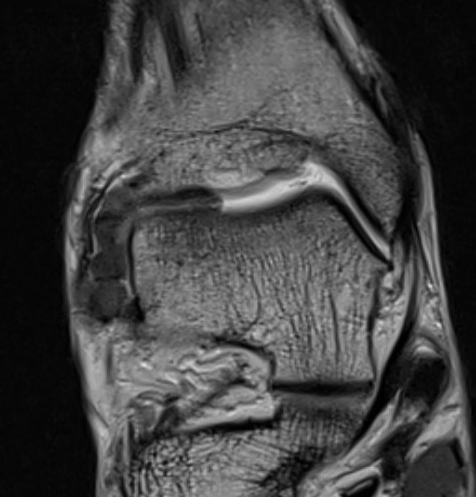

PVNS anterolateral gutter ankle

PVNS with ankle joint / talus erosion